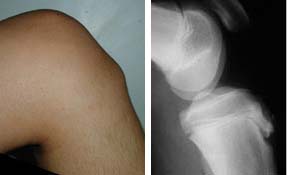

A menudo se los síntomas se presentan con comienzo vago e intermitente de dolor al arrodillarse, saltar o correr. Se incrementa tras la práctica deportiva y tiene un curso oscilante en el tiempo. Dolor a punta de dedo sobre la tuberosidad tibial que en ocasiones se acompaña de tumefacción.Busca atención médica si se presenta dolor, tumefacción u otros cambios inflamatorios en la región de la rodilla durante la actividad física que limite la realización de dicha actividad.

También es posible que se solicite una radiografía simple en la cual se pueden observar irregularidades, fragmentación, reestructuración, aparición de osículos independientes, ensanchamiento óseo e imagen en gota de cera de la epífisis tibial superior.